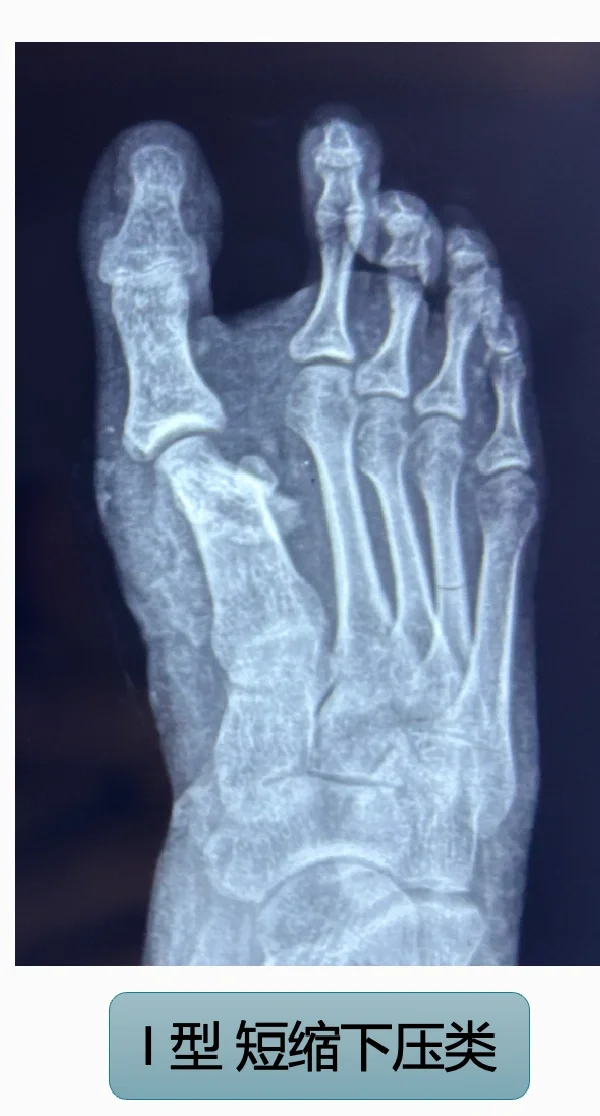

微创术后畸形~~一种新型畸形